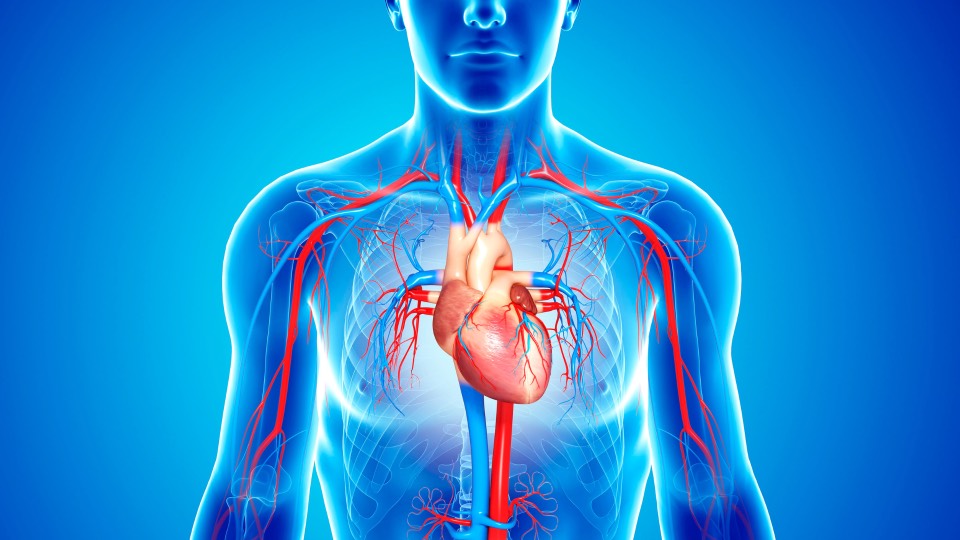

Learn More About PRS for Coronary Artery Disease

Explore this presentation on coronary artery disease genomics/PRS to discover how genomic risk evaluation supports early identification, prevention planning, and smarter cardiovascular care.